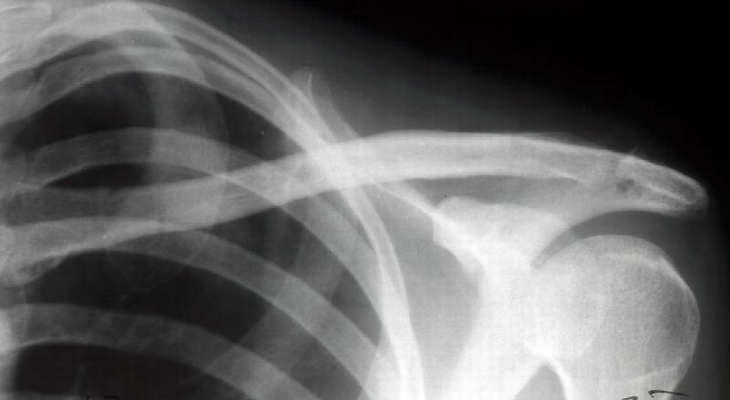

Since we have no experience with external fixation of the clavicle, we did not use this method. However, it is very interesting to see. We elected to use a T plate with a screw into the coracoid as shown in the X-ray below.

AM>We elected to use a T plate with a screw. Any comments would be appreciated.

It is a very interesting fixation but i think that the coracoid screw insertion is a little bit difficult . I have some experience in doing coraco-clavicular screw fixation and I found marked difficulty to introduce the screw.